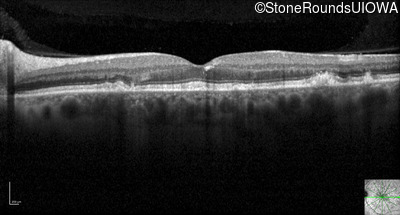

Optical Coherence Tomography - Right - 20/20 -1 sc

Exemplar / OCT Stack